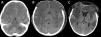

Acute fulminant cerebral edema is a type of rapidly progressive encephalitis that occurs in children and is associated with significant morbidity and mortality.

We present a clinical case with seizures, rapid neurological deterioration and the early appearance of cerebral herniation signs. Although the radiological tests were initially normal and there are no established parameters that predict the evolution of encephalitis to a rapidly progressive subtype, the clinical evolution forced to consider the decompressive craniectomy due to the lack of response to the medical management of the cerebral edema. It may be necessary take a brain biopsy to confirm the etiology of the encephalitis origin of acute fulminant cerebral edema. The objective of surgery should be not only to increase survival, but also to reduce subsequent neurological sequelae.